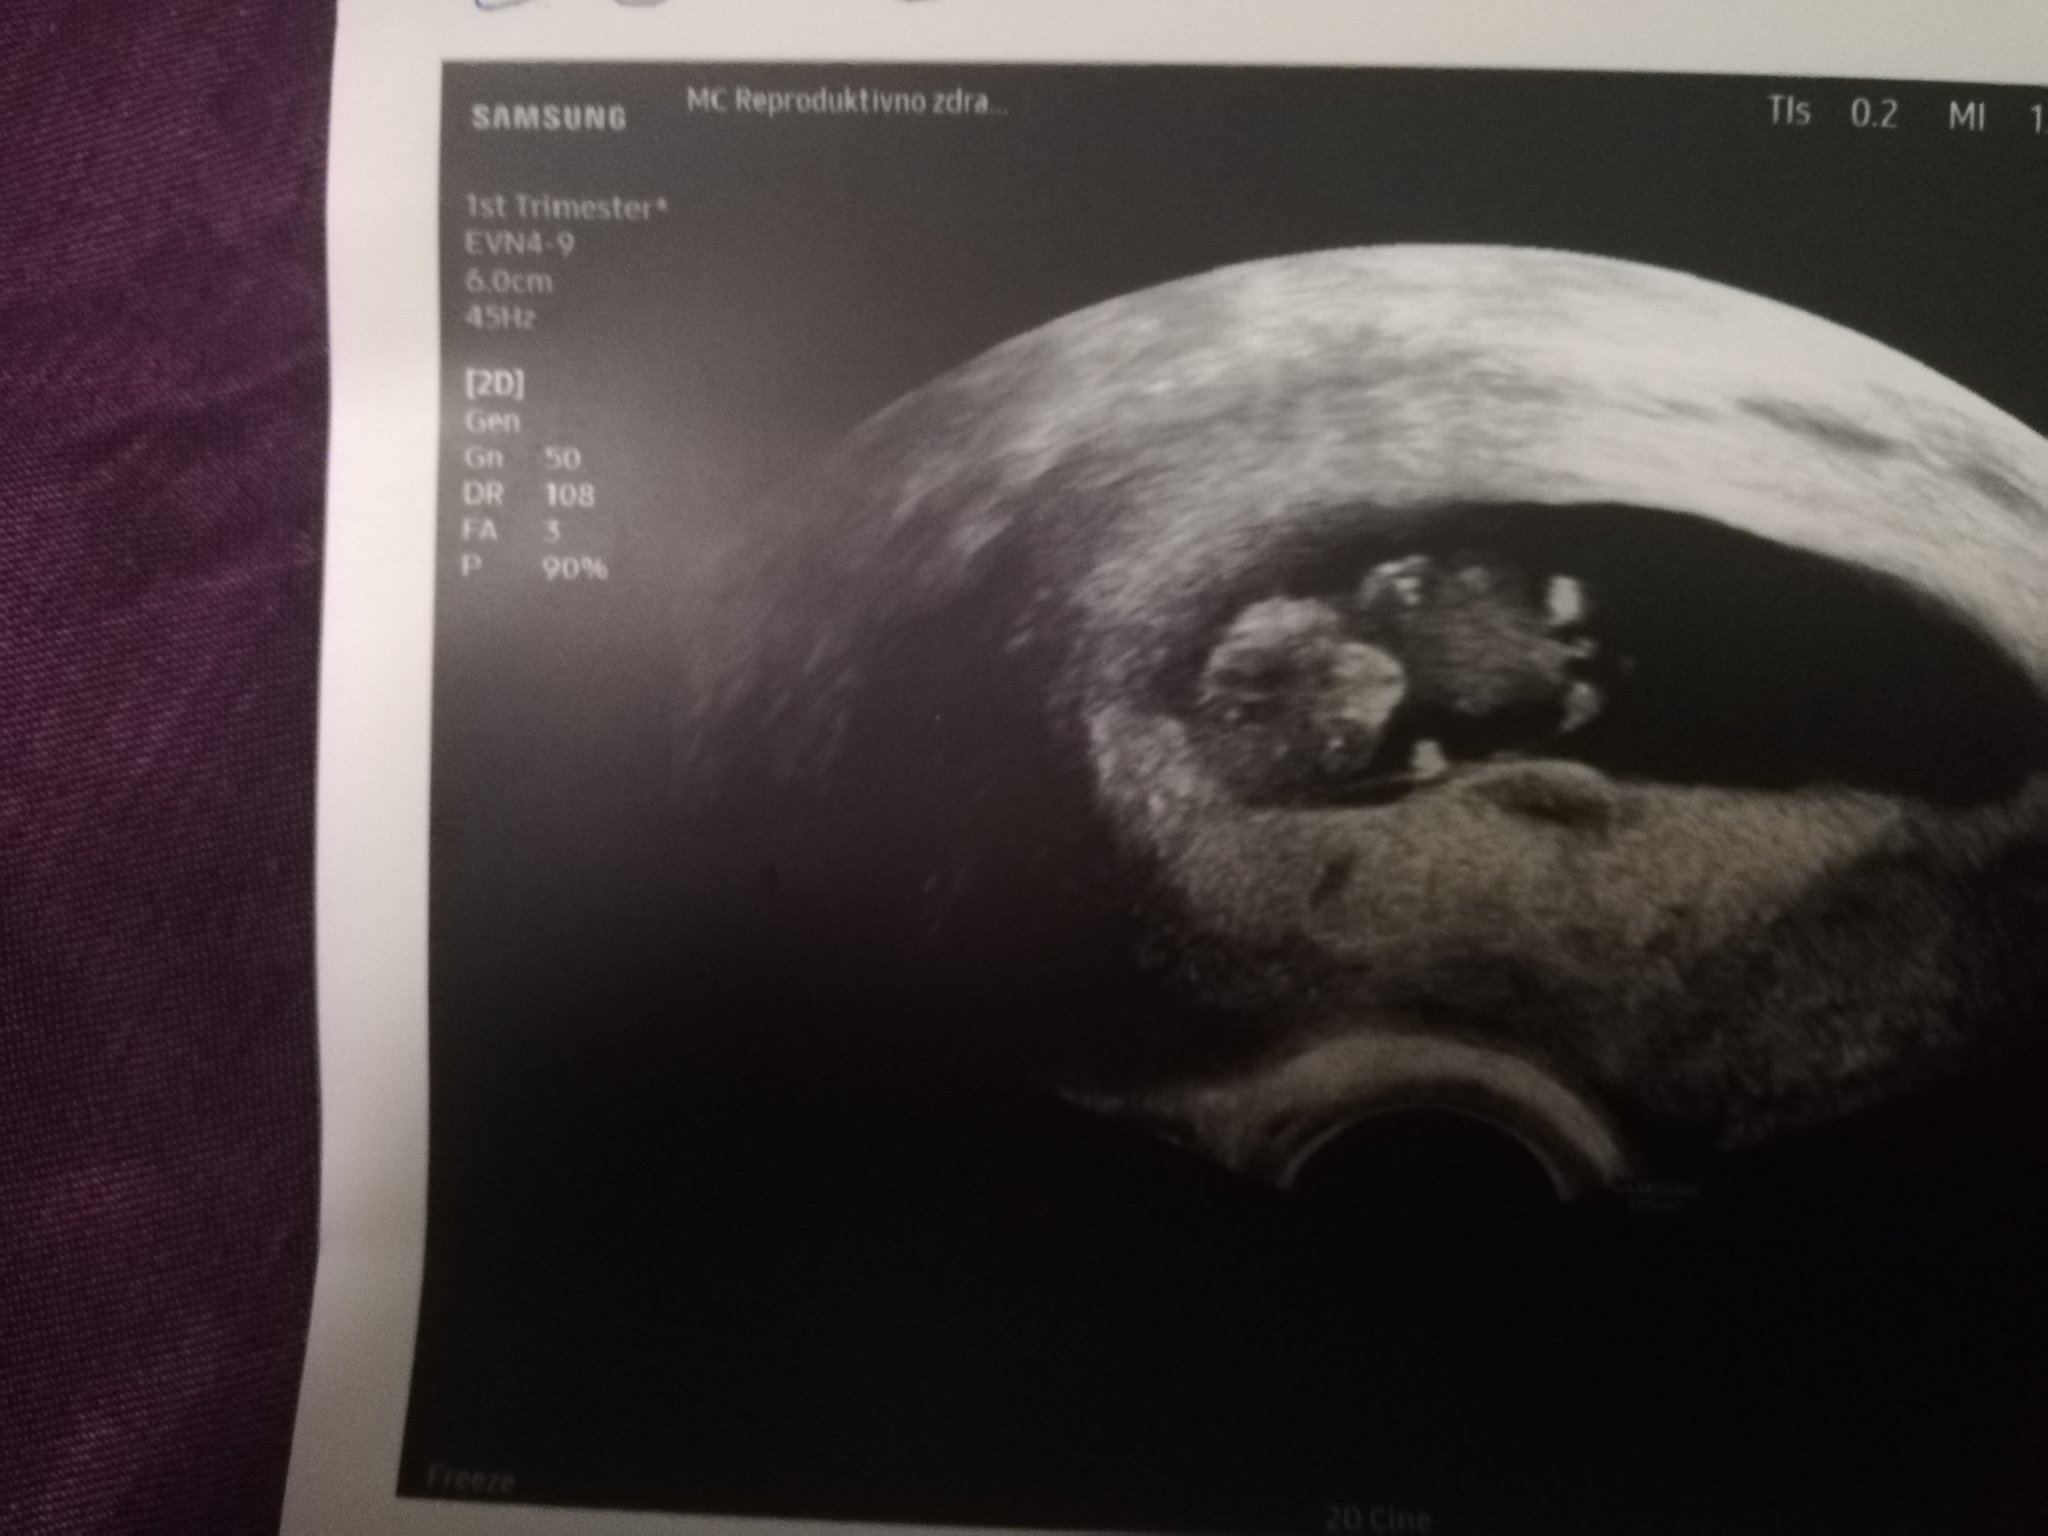

Кога се прави ранната фетална морфология?

Кога трябва да е следващият преглед след 6 седмици и 4 дни?